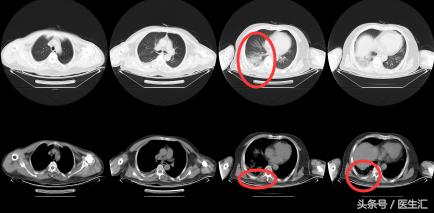

【 胸部 CT】2016.10.05

结果示:

本病例表现很普通,在临床上经常会碰到这种类型的,拿到这个病例首先可能会考虑是肺炎,但是真的是肺炎吗?为了明确诊断,再次详细问了患者的病史,下面来看看患者的病史特点,然后进行分析:

治疗后复查胸部CT(2011.11.18)